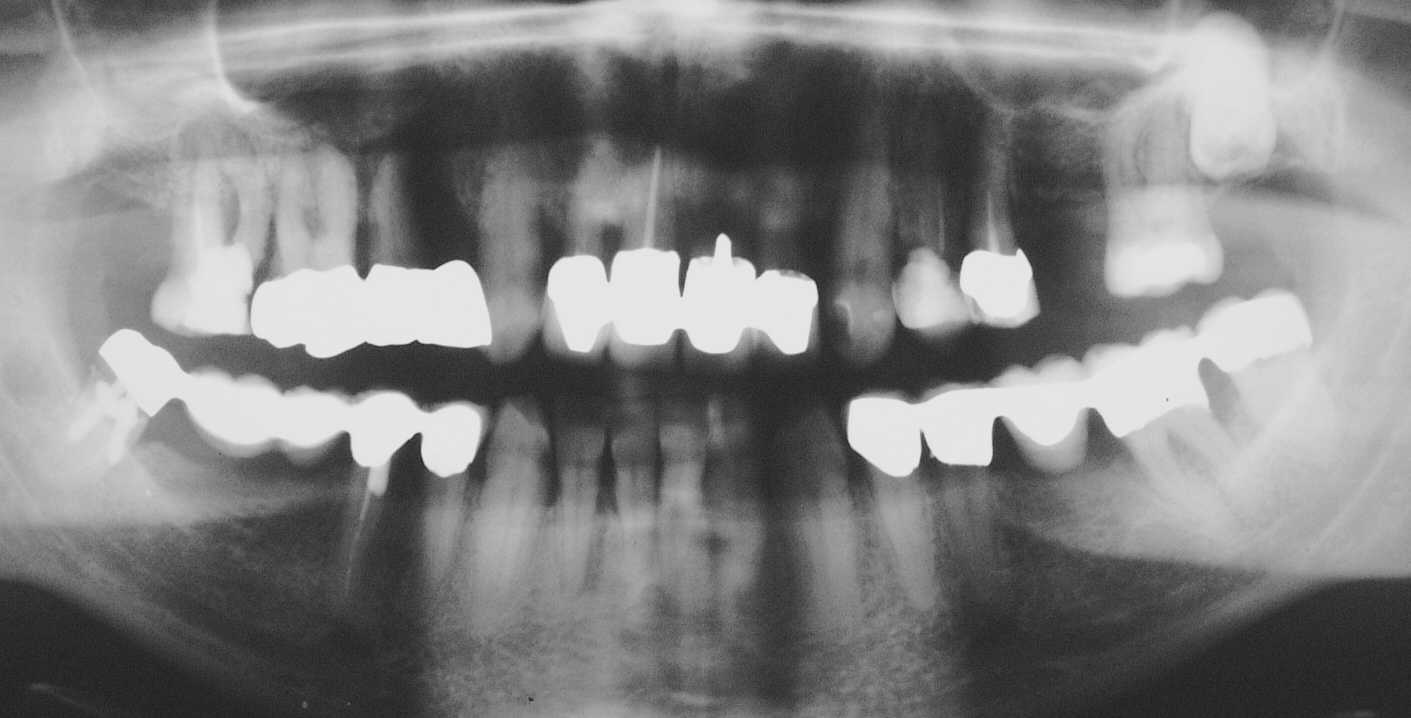

Solche umfassenden Rehabilitationen kann man, wenn man ruhig schlafen will, nur eingliedern, wenn man sich praktisch 100%ig auf seine Endodontie verlassen kann (Timbuktu-Methode)